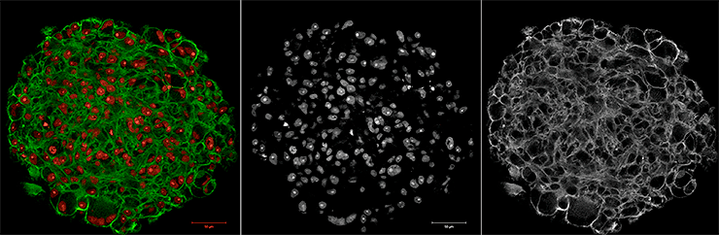

Мышечная дистрофия Дюшенна, поражающая одного из трех-пяти тысяч мальчиков, связана с мутациями в гене DMD, кодирующем белок дистрофин. В норме дистрофин связывает актиновый цитоскелет миоцитов с внеклеточным матриксом, а в отсутствие функционального белка сокращения мышцы приводят к разрушению целостности мембран миоцитов. Российские исследователи предложили новую модель для изучения дистрофии Дюшенна на основе первичных миобластов мышей с мутантным дистрофином. Помогут ли мышиные миобласты в борьбе против дистрофии Дюшенна? Давайте разбираться.